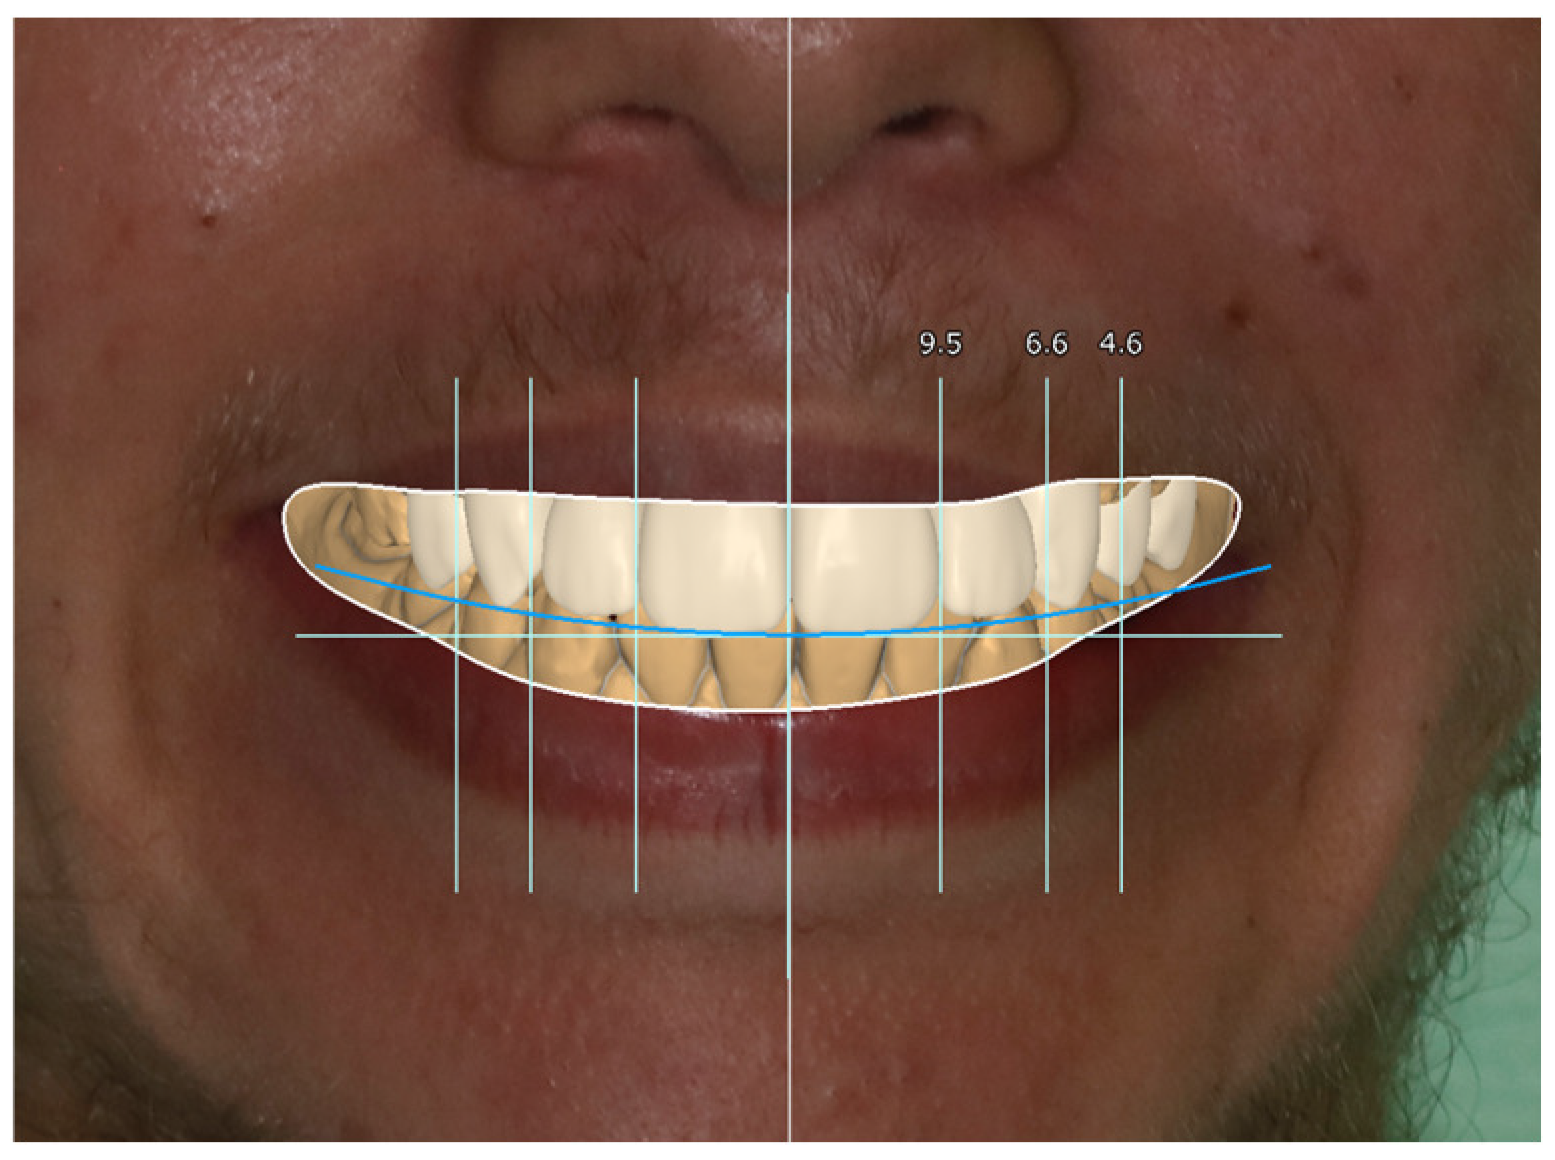

2. Case Report